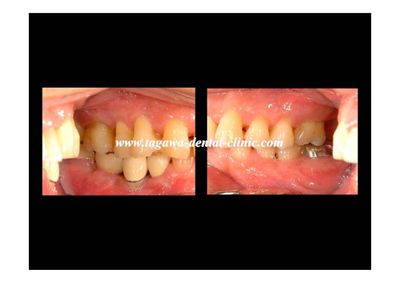

歯周病の進行と咬合力の影響について、院内勉強会にて私の症例の紹介を行いました。 症例では治療方法の優劣を示すものではなく、咬合と歯周状態の関連を検討した内容として紹介しています。

症例の概要

患者さん:60歳男性

重度の歯周病に加えて、上顎が下顎を覆うように咬合する Angle分類でクラス?の咬合関係でした。

クラス?症例は前歯誘導(かみ合わせの誘導)が得にくいことがあり、 治療計画の立案には慎重な分析が必要です。